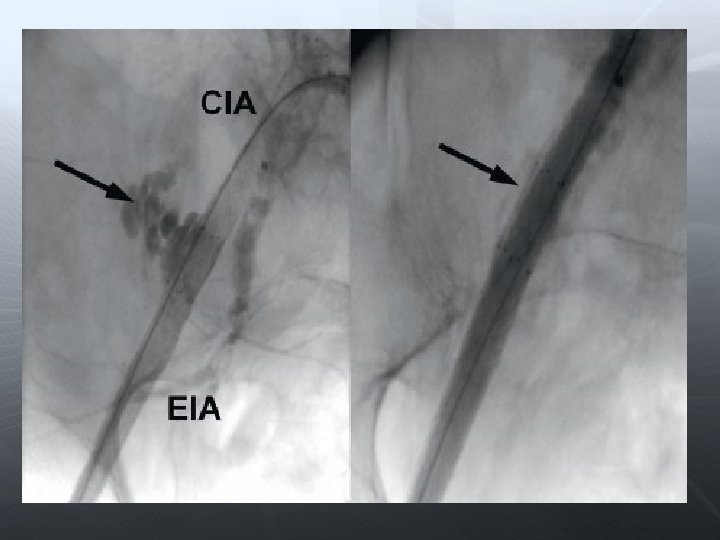

Darlık Oklüzyon Aorto-iliak Femoral-popliteal Infrapopliteal

PTA’ya yetersiz yanıt veya akımı engelleyen diseksiyon varlığında PTA’dan üstün olduğu bilinen damarlarda İlyak/subklaviyan a. oklüzyonlarında PTA’nın riskli olduğu alanlar